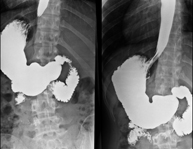

Técnica mediante la cual, utilizando rayos X, se obtienen imágenes de la columna lumbar para su estudio. - TEGD (Tránsito Esófago – Gastro – Duodenal)

Prueba diagnóstica que consiste en obtener imágenes radiológicas en movimiento del esófago, el estómago y el duodeno mediante el empleo de rayos X (fluoroscopia) y de un contraste opaco baritado que se administra por vía oral. - Tránsito intestinal

- Hipsterosalpingografía (HSG)

Prueba diagnóstica que consiste en la visualización y el estudio del útero y las trompas de Falopio mediante el empleo de rayos X y un medio de contraste. La paciente deberá realizar un tratamiento antibiótico profiláctico. Se recomienda la toma de un sedante suave una hora antes de la prueba. - Colangiografía Trans-Kher